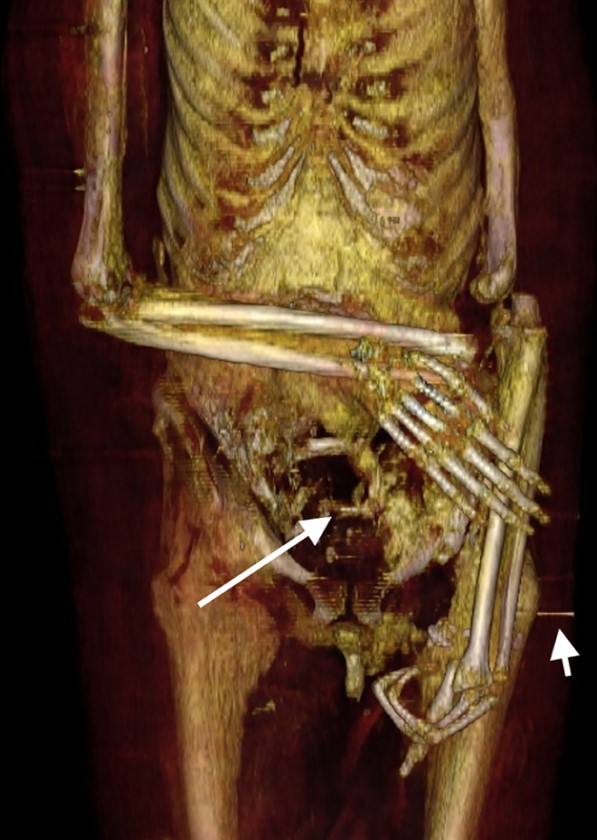

Cẳng tay phải được gập ở phần khuỷu tay và bắt chéo ngang bụng dưới. Cánh tay trái đã bị trật khớp và phần cẳng tay trái được đặt dọc theo bên trái của cơ thể. (Ảnh: Đăng dưới sự cho phép của Sahar N. Saleem và Zahi Hawass)

Hai ngón tay bị thiếu của bàn tay trái được đặt bên trong khoang cơ thể (nhìn theo hướng mũi tên dài màu đen). (Ảnh: Đăng dưới sự cho phép của Sahar N. Saleem và Zahi Hawass)

Bàn chân phải của xác ướp [pharaoh] Amenhotep I với những chiếc đinh có khả năng được ghim vào để cố định vị trí của mảng gỗ với các lớp bọc xung quanh. (Ảnh: Đăng dưới sự cho phép của Sahar N. Saleem và Zahi Hawass)

Bằng chứng của những kẻ trộm mộ cũng đã được hiển hiện. Cánh tay trái đã bị trật khớp và rồi được bọc lại dọc theo cơ thể xác ướp. Tuy nhiên, cánh tay phải của xác ướp đã cong lại ở phần khuỷu tay và phần cẳng tay đặt lên bụng, cho thấy rằng cả hai cánh tay có thể đã từng được bắt chéo theo một dạng thức tương tự. Hai ngón tay của bàn tay trái cũng bị tháo rời, có thể là do những kẻ trộm mộ, và nằm bên trong một lỗ hổng lớn của thành khoang bụng. Đáng chú ý hơn, cổ của xác ướp đã bị cắt đứt, phần đầu lìa ra và được gắn lại bằng một dải vải lanh được xử lý qua nhựa cây với một tấm bùa bảo hộ được đặt bên dưới.